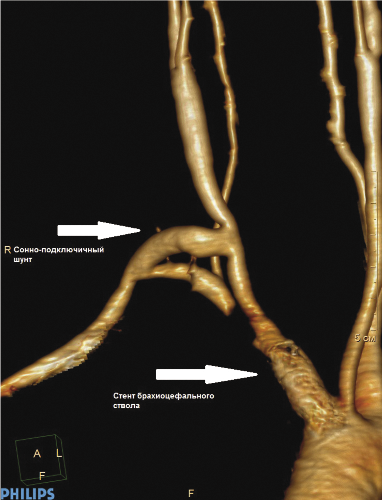

Пациент К., 55 лет, поступил в отделение сосудистой хирургии ФГБУ ФНКЦ ФМБА России 30.08.2017 г. с жалобами на частые головные боли, выраженные головокружения и пошатывания при ходьбе, которые беспокоят в течение 2 лет. Эпизодов острого нарушения мозгового кровообращения (ОНМК) не было. В анамнезе АББШ, неоднократные тромбэктомии и реконструкции дистальных анастомозов с обеих сторон. При физикальном осмотре отсутствует пульсация на ППА, градиент артериального давления на верхней конечности 40 мм рт. ст. При дуплексном сканировании выявлены окклюзия ППА в первом сегменте с ретроградным кровотоком по позвоночной артерии, коллатеральный кровоток по правой плечевой артерии. При КТ с контрастным усилением визуализированы критический стеноз БЦС, окклюзия ППА в первом сегменте без значимых изменений позвоночных и сонных артерий в экстра- и интракраниальных отделах (рис. 1, 2). В связи с наличием клинических проявлений сосудисто-мозговой недостаточности (СМН) на фоне выявленной патологии БЦА были определены показания к оперативному лечению в целях профилактики ОНМК.

Рис. 1. КТ с контрастным усилением: критический стеноз брахиоцефального ствола

Рис. 4. КТ с контрастным усилением через 6 месяцев после операции: 3D–реконструкция, нормальная проходимость сонно-подключичного шунта и имплантированного стента брахиоцефального ствола

Рис. 5. КТ с контрастным усилением через 6 месяцев после операции: нормальная проходимость сонно-подключичного шунта и имплантированного стента брахиоцефального ствола